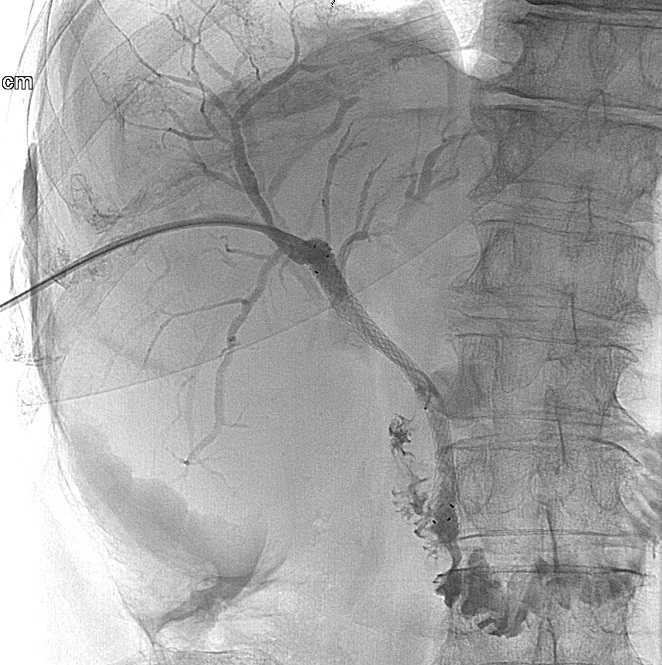

After a diagnostic PTC is successfully performed and a guide wire is positioned over the stenotic or occluded segment of the choledochal duct an external-internal drain (PTD) can be installed. (Figure 23.) If desired, a self expanding metallic stent could be used to override the stricture (Figure 24.)

Image

Figure 23. – PTD (Percutaneous transhepatic external-internal drainage)